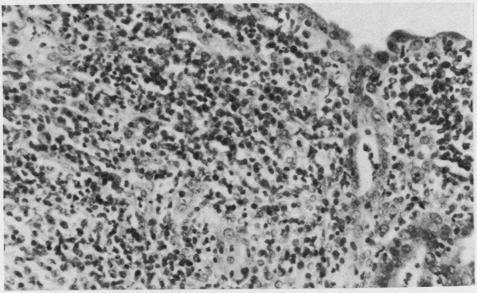

Endometrial biopsies were obtained from 32 women with suspected pelvic inflammatory disease, of whom 23 (72%) had histopathological evidence of endometritis. Chlamydia trachomatis was isolated from the endometria of nine (39%) women (chlamydia group) but not from the other 14 (non-chlamydia group). Severe plasma cell endometritis and lymphoid follicles with transformed lymphocytes were significantly more common in the chlamydia group than in the non-chlamydia group. This suggests that C trachomatis is an invasive endometrial pathogen which often causes severe inflammation. The association was independent of predisposing factors such as use of intrauterine contraceptive devices.

对32名疑似盆腔炎的女性进行了子宫内膜活检,其中23名(72%)有子宫内膜炎的组织病理学证据。从9名(39%)女性的子宫内膜中分离出沙眼衣原体(衣原体组),而在其他14名女性(非衣原体组)中未分离出。重度浆细胞性子宫内膜炎和伴有转化淋巴细胞的淋巴滤泡在衣原体组中比非衣原体组中更为常见。这表明沙眼衣原体是一种侵袭性子宫内膜病原体,常引起严重炎症。这种关联独立于诸如使用宫内节育器等易感因素。